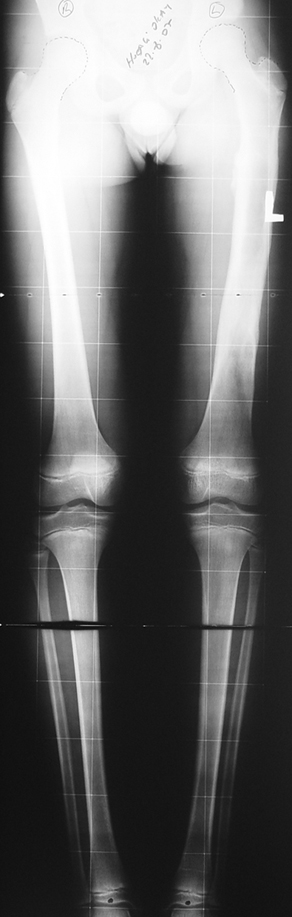

Appropriate radical debridement necessitates excision of all necrotic bone and soft tissues, and frequently causes instability at the involved extremity. The remaining bone and soft tissue defect has to be fixed and reconstructed. The distraction osteogenesis method of Ilizarov is used successfully for achievement of union, correction of the deformity, elimination of limb length inequality and reconstruction of segmental bone defects.

The duration of external fixation (external fixation index) depends on the amount of distraction required, and the extremity is prone to complications during this period. After the distraction phase is completed, the external fixator remains in place during the consolidation phase, which lasts twice as long as the distraction phase; but this period is hardly tolerated. If the external fixator is removed before sufficient consolidation is achieved, fractures, deformity and shortness will be the result. In our department, ‘lenghthening over nail’ method is used in order to decrease the external fixation index and increase patient comfort and activity level. In this method, the intramedullary nail is statically locked after the completion of the distraction phase, and external fixator is removed. The extremity is stabilized by the intramedullary nail during consolidation phase. In this way, complications due to long external fixation index or early removal of the external fixator are avoided.